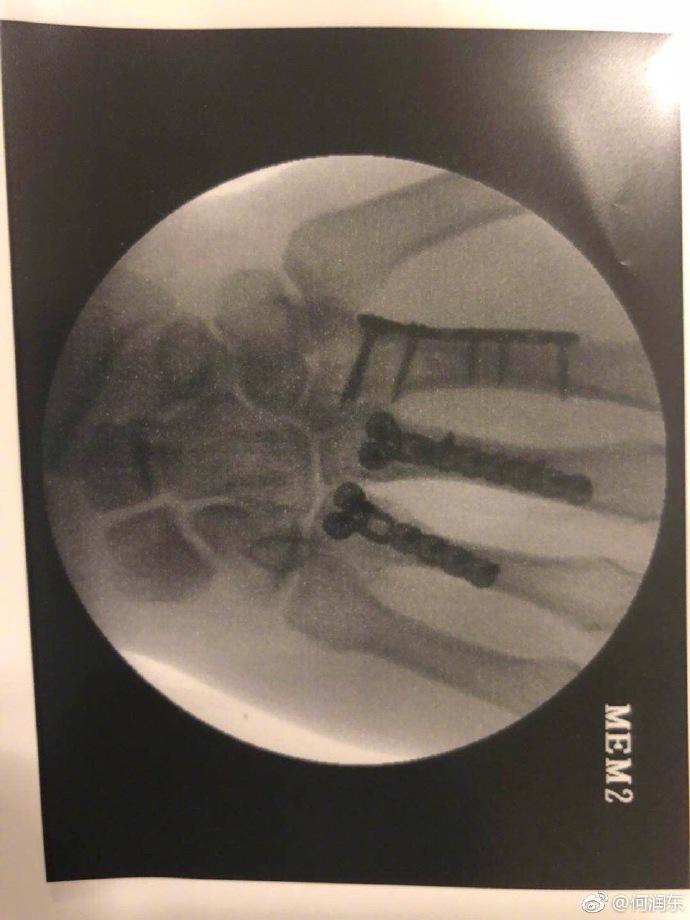

他受伤的伤情才不止这一点,另一张X光片明显看得出来有三根手指都做了固定处理。黑乎乎的阴影,看着也是让人毛骨悚然。

这般惨痛,没想到何润东心情似乎还是不错的,三根钢爪子已经有了,“当我能摆脱残障式健身的那一刻,我将升级为金刚狼。”

不知道他是在拍戏中受的伤,还是健身中。细看X光拍摄的时间,何润东这次受伤是在4月28日。五一劳动节的时候他还用裹着绷带的手给劳动者致敬,裹这么厚,当时就应该想到他伤得重才是。